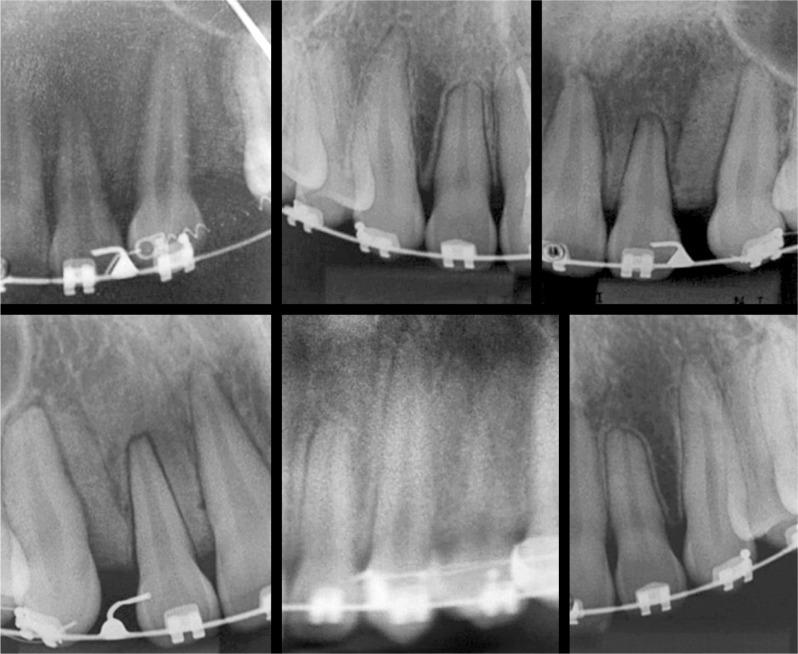

Gingival crevicular fluid was collected from two groups of 60 patients each, with and without external root resorption. Samples were extracted by means of various methods of protein extraction. SDS-PAGE gels were used to assess the quality of the method which was subsequently tested during isoelectric focusing of 2-DE gels taken from samples of patients with and without the disease.

Milli-Q ultrapure ice cold water, without precipitation for gingival crevicular fluid protein extraction, proved the method with greatest sharpness to detect protein bands. Additionally, it allowed two-dimensional electrophoresis to be performed.

The new protein extraction protocol does not interfere in isoeletric focusing of 2-DE gels. Furthermore, it provides the greatest sharpness in detecting protein bands of SDS-PAGE gels. This will allow mapping and searching of new external root resorption markers, particularly due to the difficulty in carrying out molecular tests with the current candidates for protein markers.